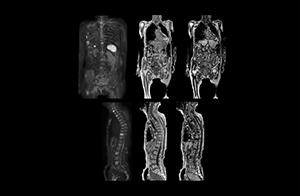

“When we limited the scan coverage to the area from neck to femur, we could fit more clinical information in approximately the same scan time. So, we added coronal mDIXON, sagittal T1-weighted, and sagittal STIR sequences to our examination, instead of performing only axial DWIBS and coronal single-shot TSE scans.”

The single shot T2-weighted TSE images are used for morphology and compared to DWIBS images to identify T2 shine-through. Sagittal STIR images are used in patients with inflammation or bone metastasis.

Coronal DWIBS is faster and improves image quality

“Switching to coronal DWIBS – rather than axial – further shortens scan time,” says Mr. Naka. “Important is that a dS SENSE factor of 5 shortens exam time while high image quality can be maintained, thanks to Ingenia’s dStream architecture.” He adds that the coronal orientation also avoids artifacts that are specific to combining axial images.

“When we use a coronal DWIBS acquisition, we can perform a full whole body examination, including other required sequences, within 30 minutes,” he says.

“This is considerably faster than the previously used exam with axial whole body DWI, which took more than 45 minutes,” he notes. “A shorter exam is more patient-friendly and allows us to also use it on patients in poor health who would have difficulty tolerating a long exam. Limiting the exam time is also helpful for scheduling, because it fits in a normal single exam timeslot.”